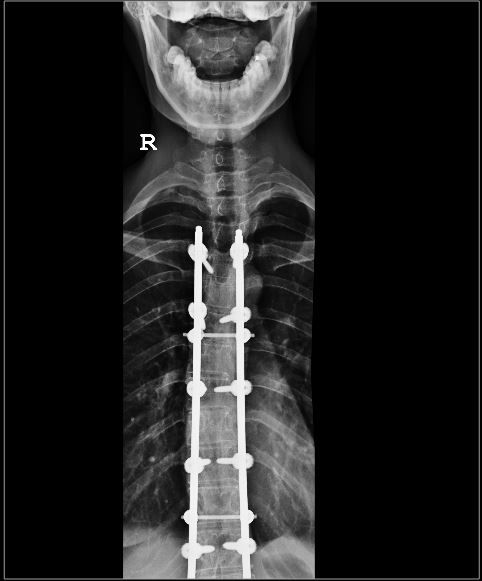

This is the implant inside my body. My spine was originally a ‘S’ shape spine.

It is not entirely straight now as you can see from the Xray..